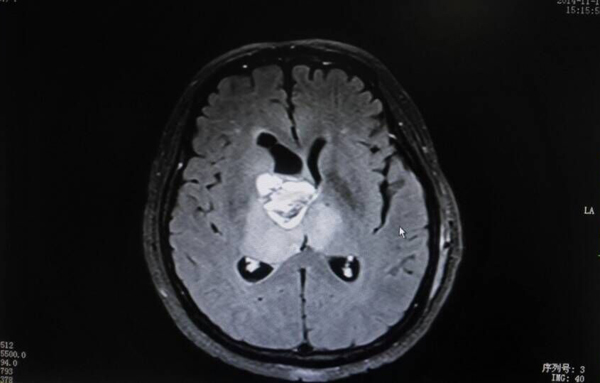

治疗前刘女士的肿瘤为33mm×30mm